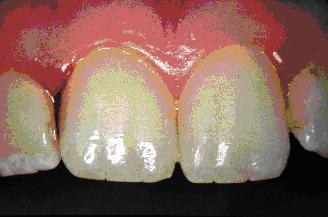

Slika 1. Vnetje dlesni s krvavitvijo pri najstnici.

Slika 2. Pobarvana mehka zobna obloga na zobeh pri isti osebi kot na sliki 1.